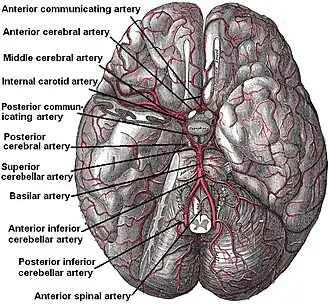

Далее внутренняя сонная артерия делится на свои конечные ветви:

- передняя мозговая артерия;

- средняя мозговая артерия.

Внутренняя сонная артерия может получать кровоток от важного коллатерального кольца мозговых артерий, более известного как виллизиев круг.

Артерии основания головного мозга.

Артерии основания головного мозга.